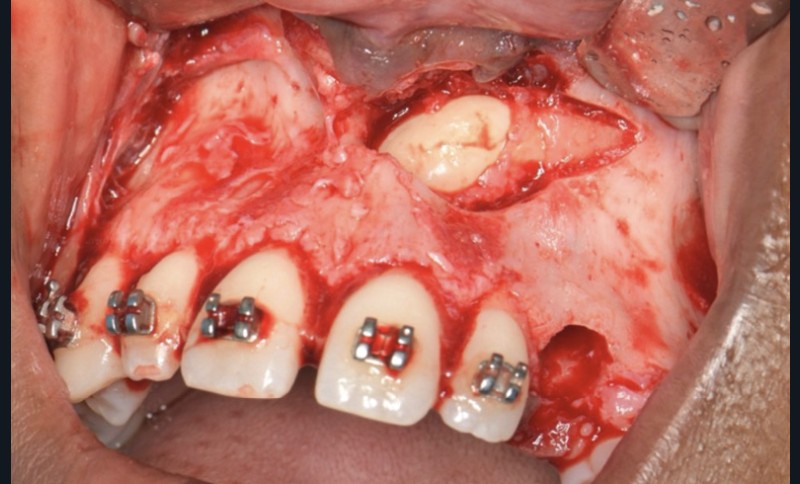

Une fois l’espace nécessaire obtenu, des cales molaires sont réalisées pour limiter les interférences occlusales avec la 23. La 63 et l’odontome sont extraits (fig. 4). Un lambeau est levé et la réplique 3D de la 23 est essayée dans l’alvéole, qui est adaptée en fonction (fig. 5). La 23 est prélevée de façon atraumatique (fig. 6) et auto-transplantée (fig. 7). Après suture du lambeau (fig. 8), une contention par arc acier 0,019×0,025’’ avec un CVI entre la dent et l’arc orthodontique est réalisée (fig. 9). Trois ou quatre semaines après l’auto-transplantation (fig. 10), le traitement endodontique est effectué (fig. 11). Un bracket orthodontique pourra être collé de façon passive, et la dent prise en charge avec un arc Niti 0,017 x 0,025’’ (fig. 12).